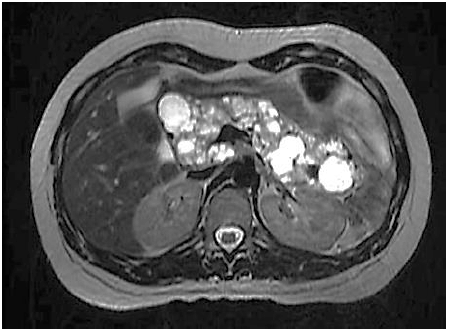

Paciente realiza ressonância magnética que individualiza múltiplas formações císticas pancreáticas conforme a imagem: